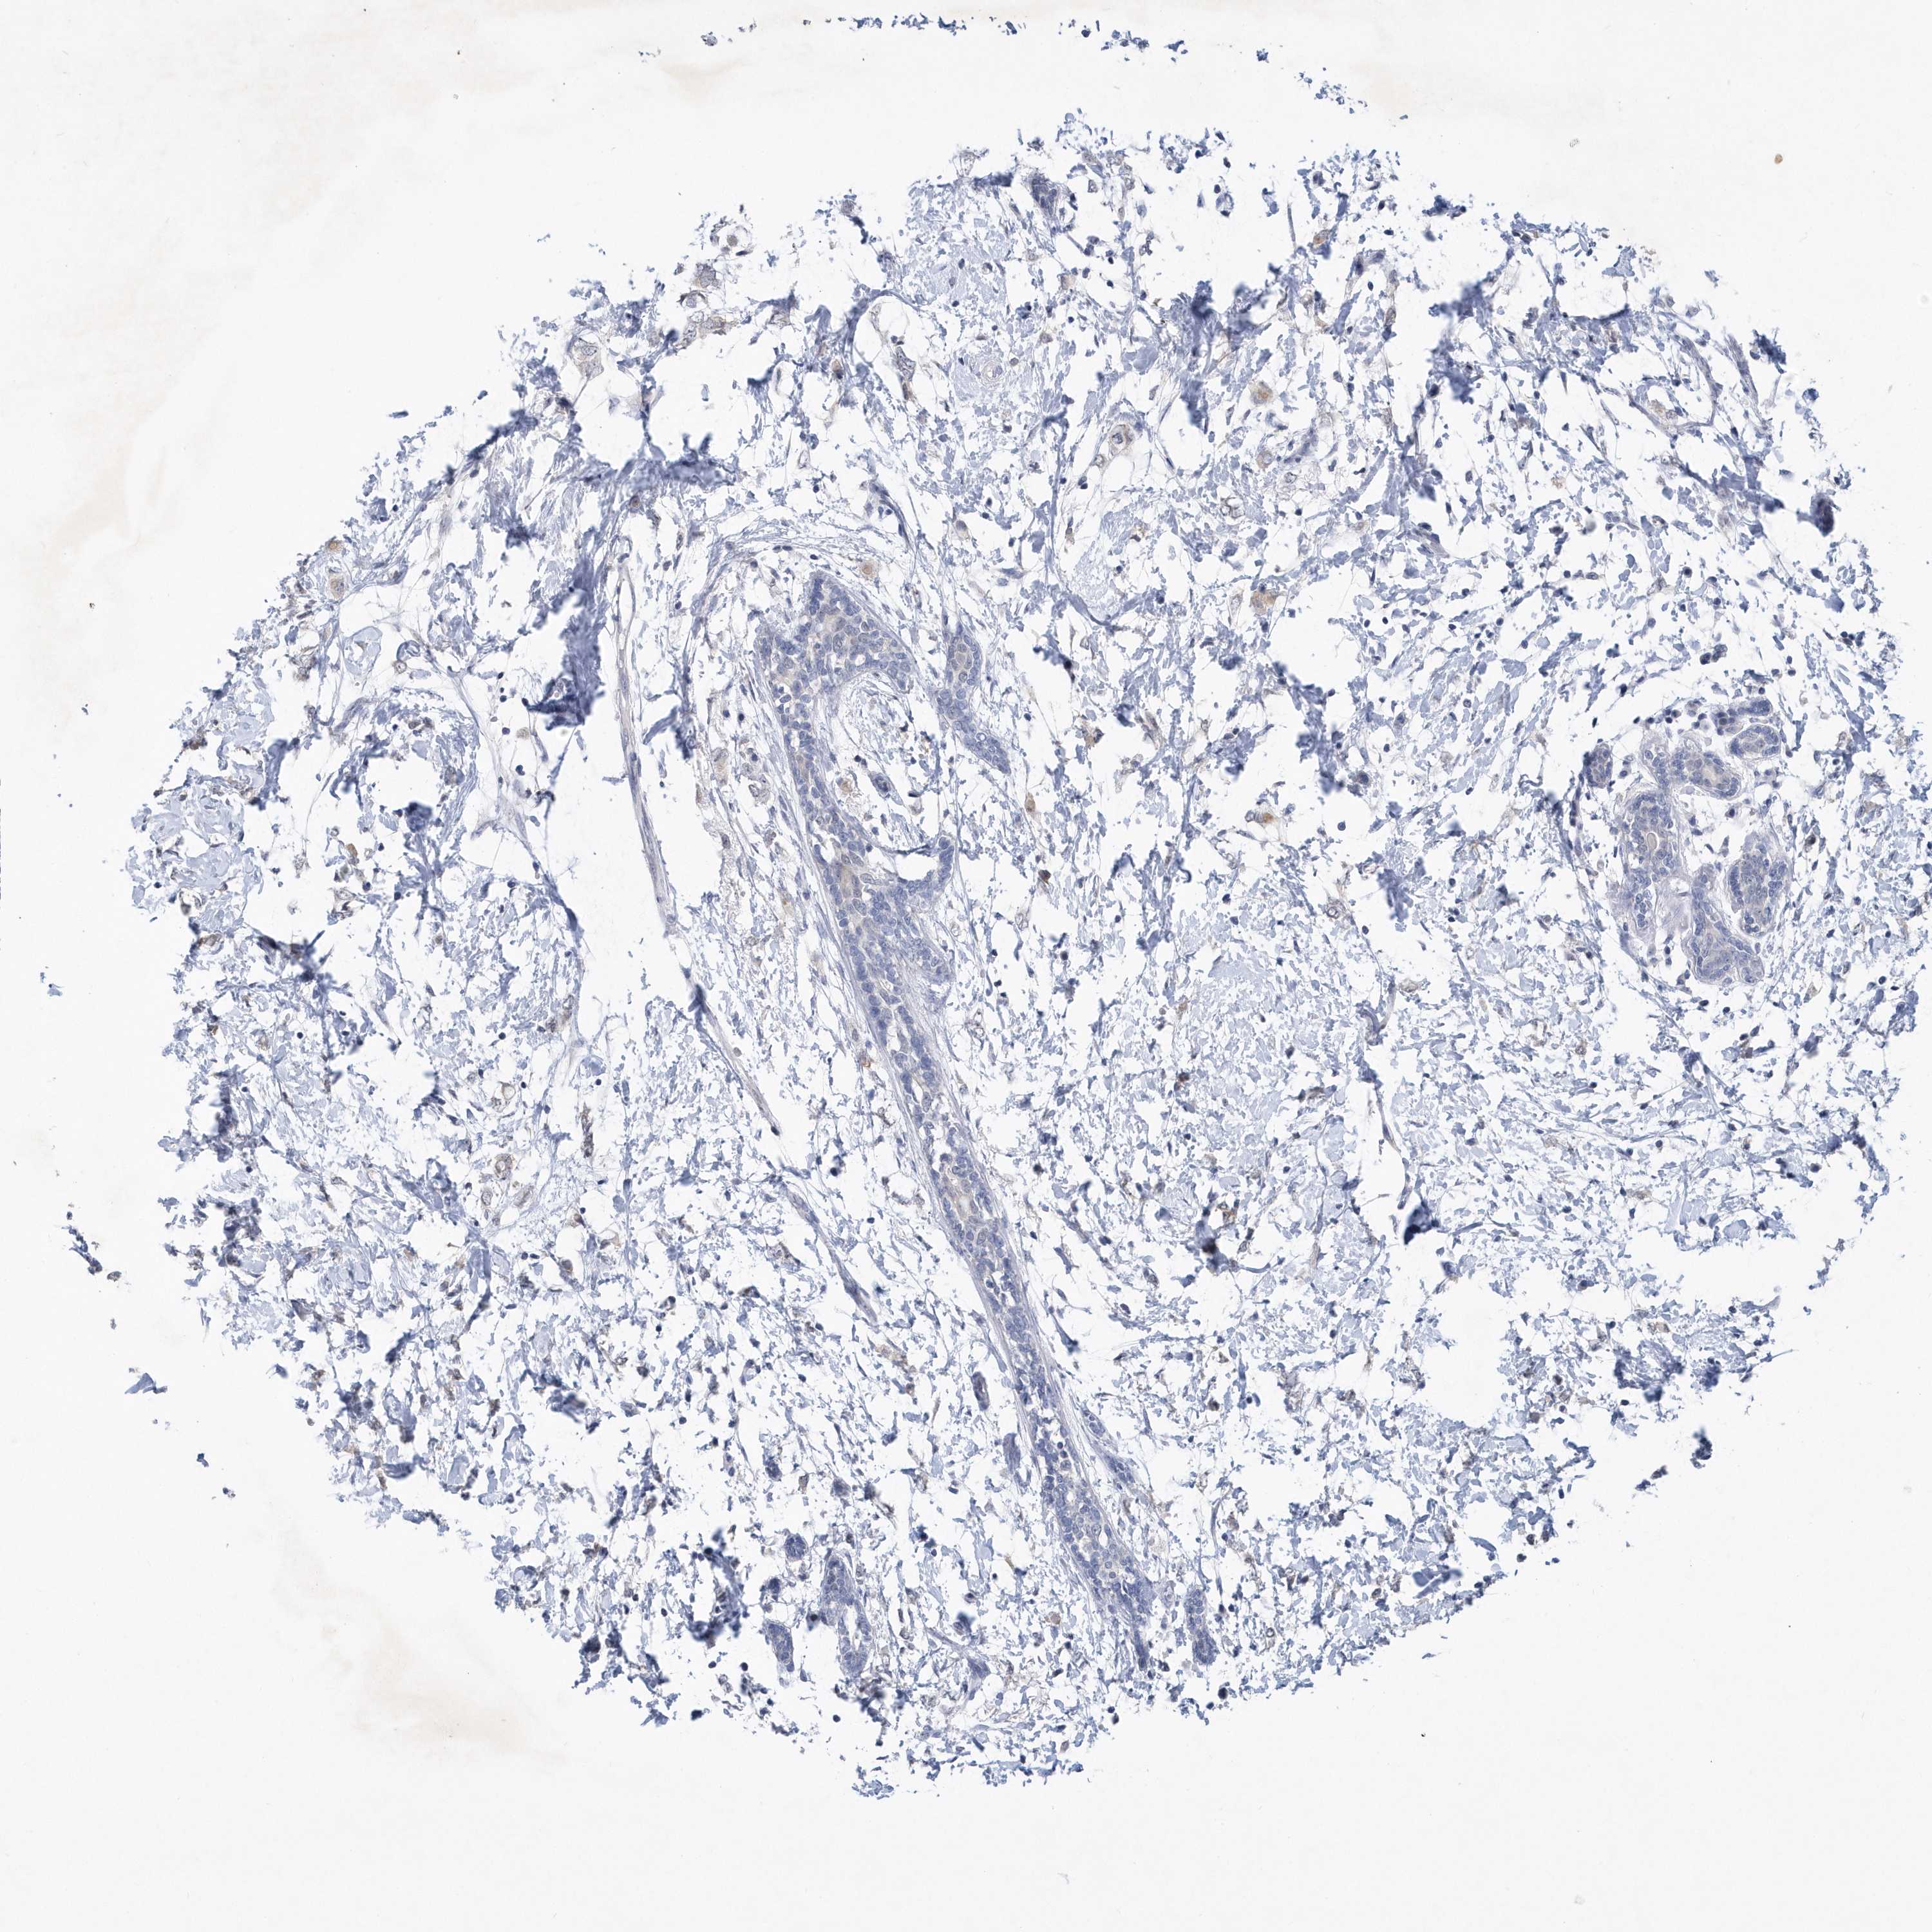

CANCER BREAST CANCER Show tissue menu

BRCA TCGA BRCA VALIDATION PROTEIN EXPRESSION

Breast cancer

Human cancer

Breast invasive carcinoma